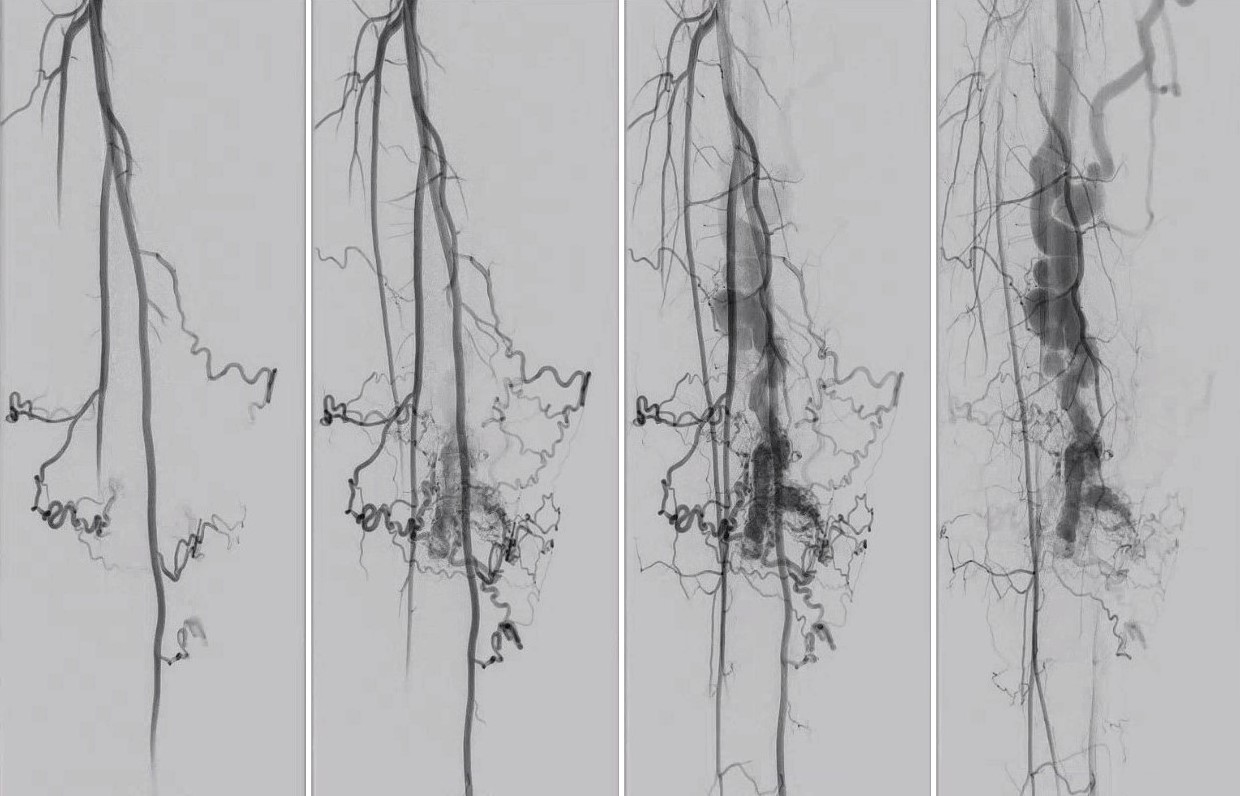

Arterioveneuze malformaties en fistels

Bij arterioveneuze malformaties en fistels is er een verbinding ontstaan tussen aanvoerende arteriën en afvoerende venen zonder dat daar een normaal capillair vaatbed tussen zit. Er is een hoge bloedstroom in deze laesies (high flow). De term arterioveneuze malformatie wordt gebruikt als het gaat om een laesie bestaande uit een kluwen van gedilateerde en abnormale vaten met hoge flow. De term arterioveneuze fistel wordt gebruikt als er een directe verbinding is ontstaan tussen een arterie en een vene. Dit kan congenitaal aanwezig zijn maar ook ontstaan door een trauma, spontaan, of iatrogeen, bijvoorbeeld als complicatie na een dotterprocedure. Ook een shunt voor dialyse kan worden beschouwd als een arterioveneuze fistel. Cerebrale arterioveneuze malformaties kunnen neurologische klachten veroorzaken zoals epilepsie of beroerte. Bij AV malformaties in de longen kan hypoxie ontstaan. Bij een grote flow door AV malformaties kan hartfalen optreden. AV malformaties zijn te herkennen aan klinische kenmerken zoals warmte of het voelen van pulsaties, en door middel van een echo (duplex).

Arterioveneuze malformatie Arterioveneuze malformatie Arterioveneuze malformatie